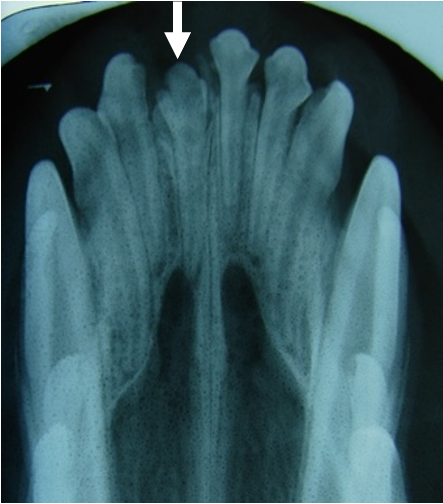

生えていない歯がいくつかあります

レントゲン写真では永久歯がありません